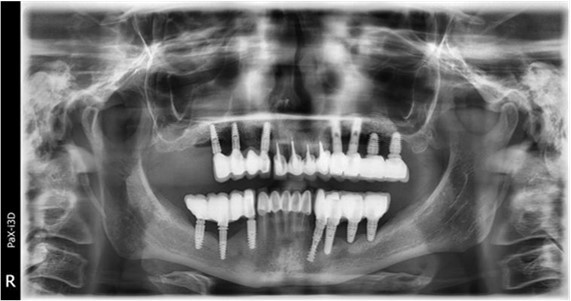

June 2022: Patient presented to our clinic for immediate-loading implant treatment At the time of presentation in 06. 2022, radiologically, advanced peri- implantitis is observed around the implants, with loss of native bone in the affected distal areas (Figure 1)

Figure 1.Panoramic overview picture before rehabilitation 06.2022

Panoramic overview picture before rehabilitation 06.2022